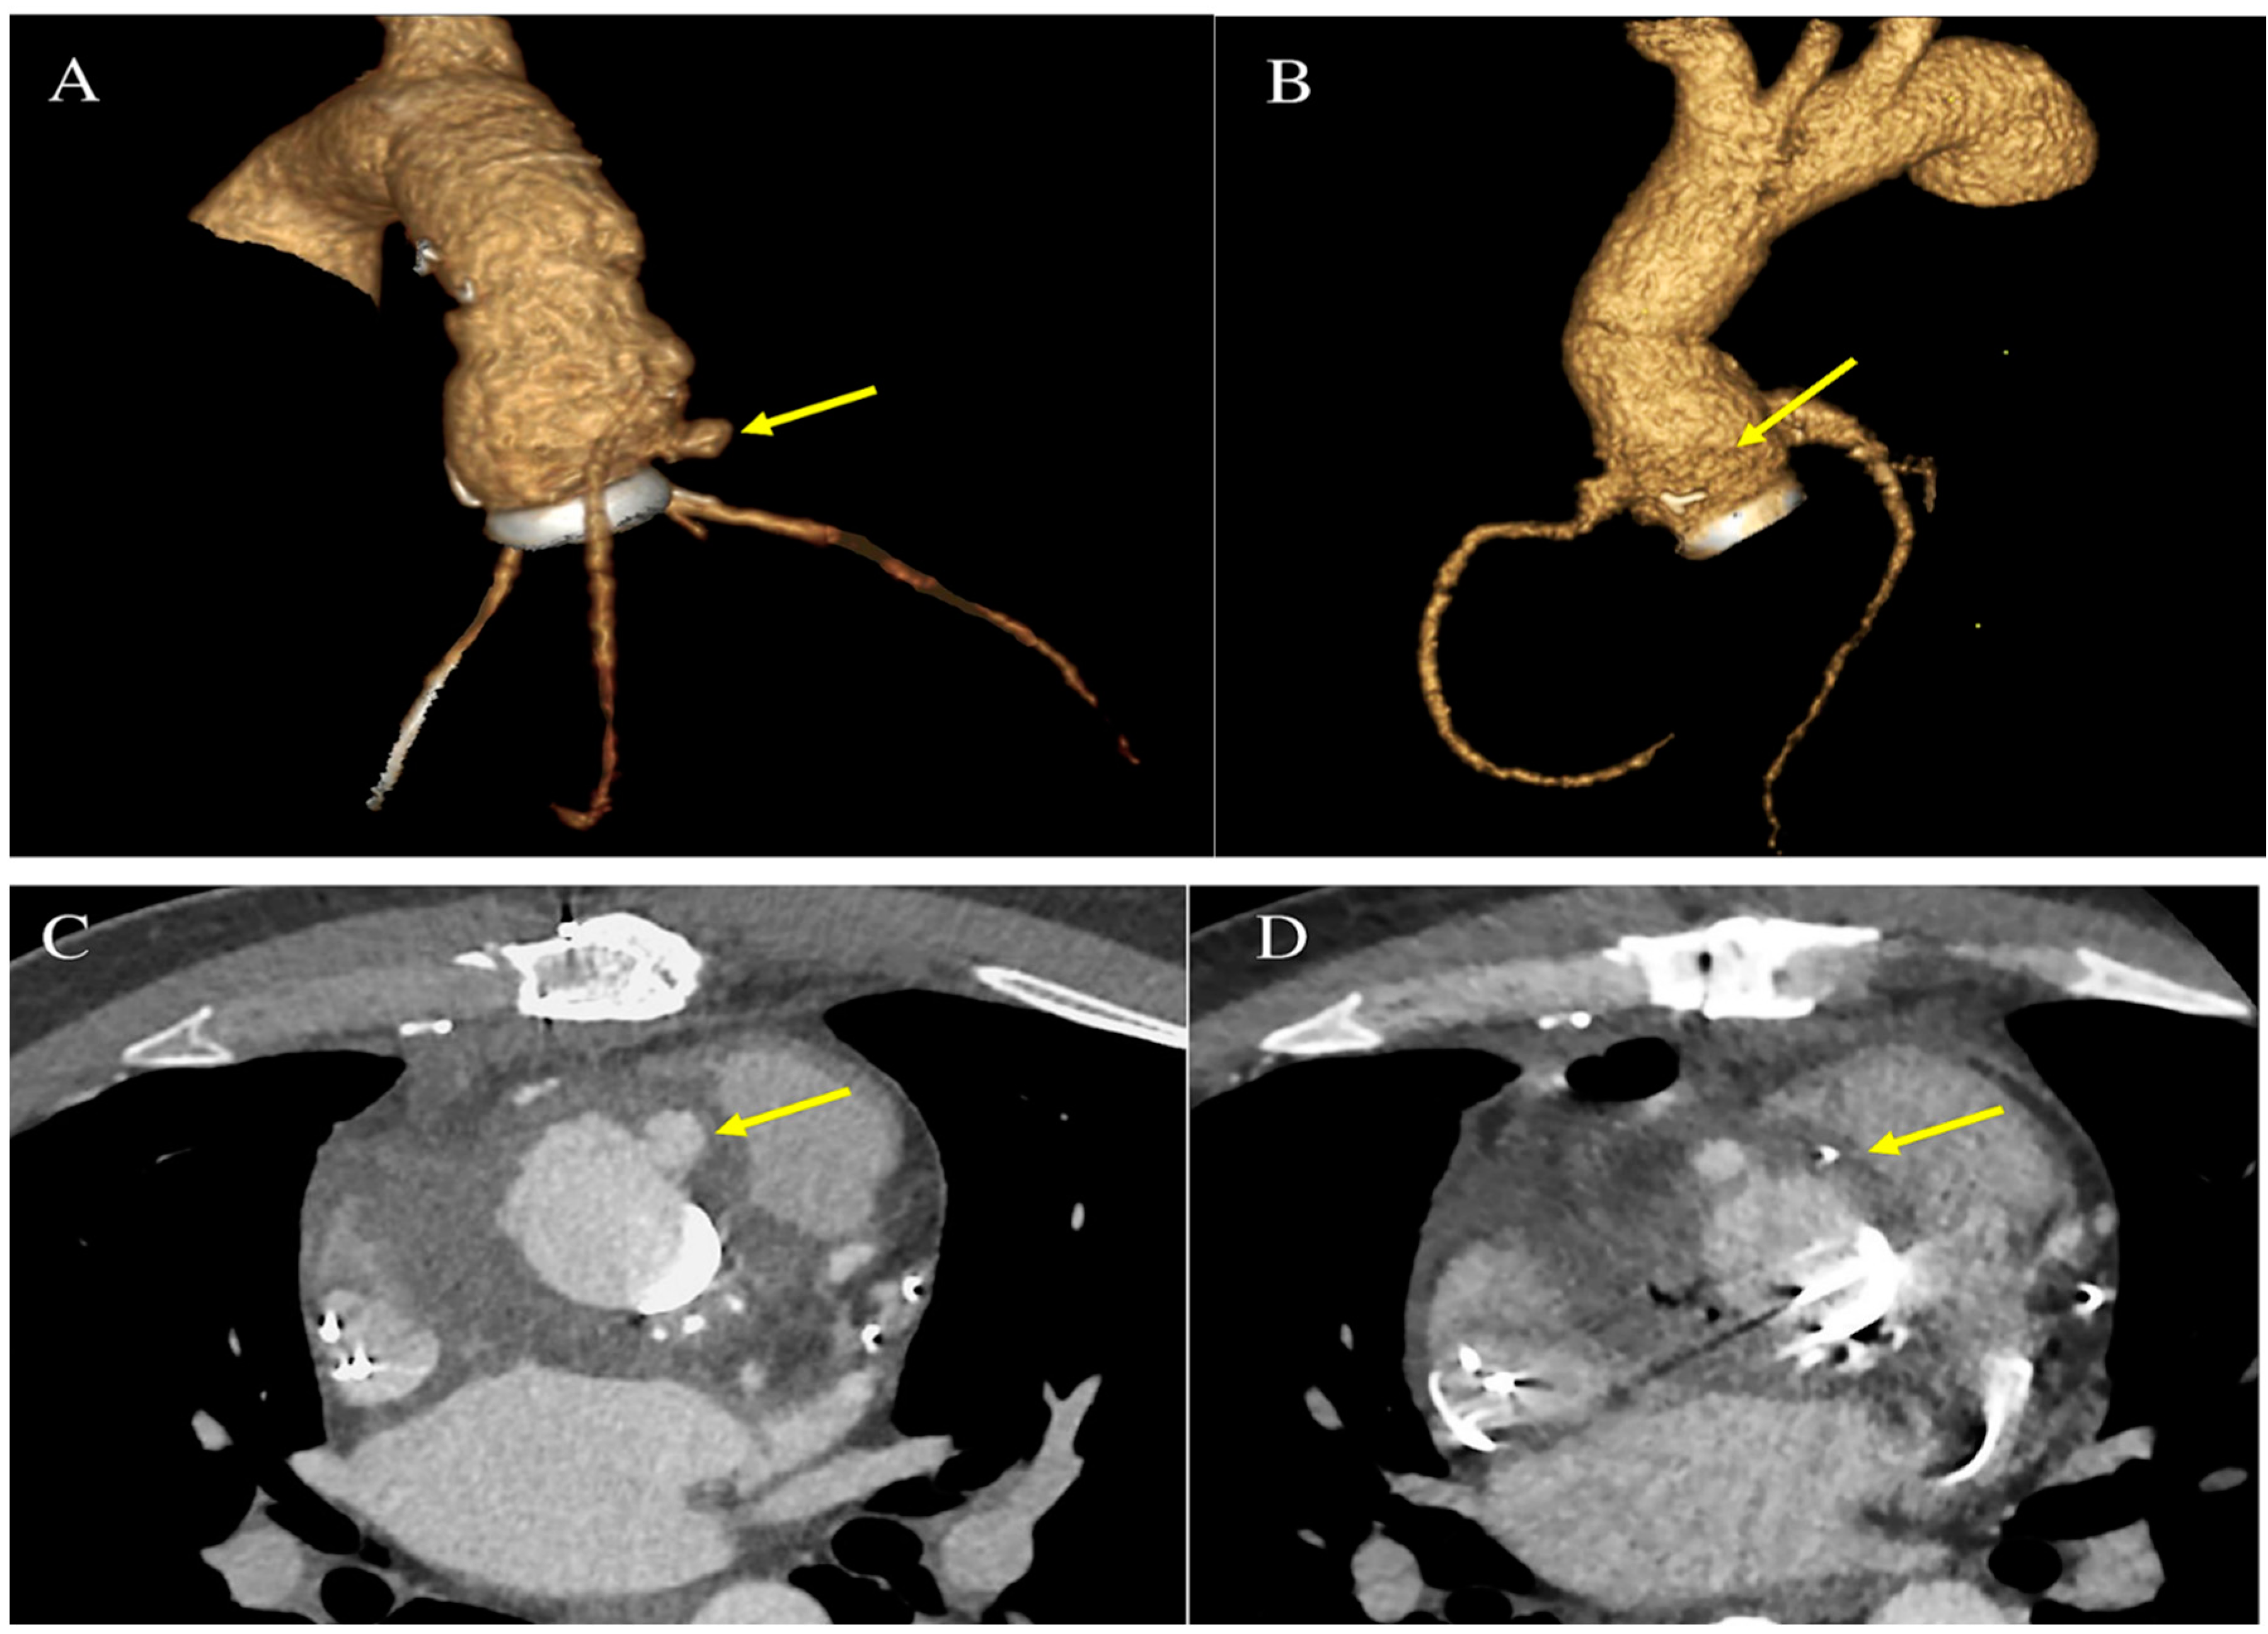

During hospitalization, transthoracic echocardiogram (TTE) was negative for vegetations and para-valvular leak; however, the presence of TAVI leaflet thickening and augmented transvalvular gradient were observed. Brain computed tomography (CT) scan showed two recent ischemic lesions which evoked a possible embolic aetiology. Transoesophageal echocardiogram (TEE) showed a mobile vegetation attached to the frame of the transcatheter prosthetic valve and an abscess in the intervalvular fibrosa. Positive blood cultures for Enterococcus faecalis completed the diagnosis of IE. A Fluorodeoxyglucose positron emission tomography/computed tomography (FDG-PET/CT) also confirmed multifocal uptake of the prosthetic. Figure 1 The patient is referred to a cardiac surgeon for consideration of aortic-valve replacement. Figure 2